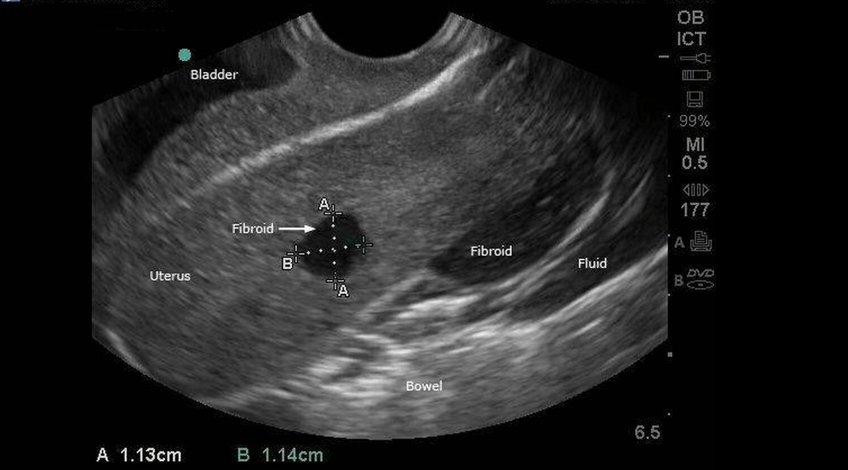

- Este método de diagóstico tiene como propósito observar afecciones en los órganos internos de la mujer, cómo quistes en los ovarios, fibromas o sangrado anormal en el útero.